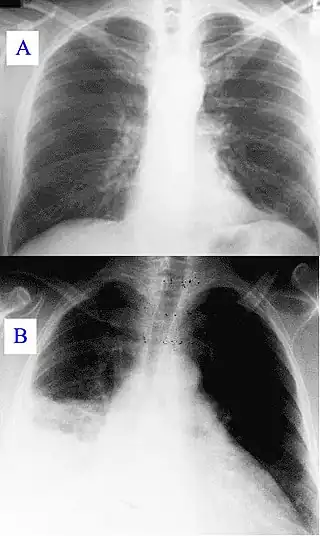

La neumonía es, por lo general, la infección aguda del parénquima pulmonar asociada a un nuevo infiltrado en la radiográfica de tórax. La neumonía puede afectar a un lóbulo pulmonar completo (neumonía lobular), a un segmento de lóbulo, a los alvéolos próximos a los bronquios (bronconeumonía) o al tejido intersticial (neumonía intersticial). La neumonía hace que el tejido que forma los pulmones se inflame, se hinche y provoque dolor. Muchos pacientes con neumonía pueden ser tratados de forma ambulatoria sin requerir ingreso hospitalario.

- Neumonía alveolar o lobar: afecta múltiples alvéolos, que se encuentran llenos de exudado pudiendo incluso comprometer un lóbulo completo; no obstante, los bronquiolos están bastante respetados, motivo por el cual se puede observar en ocasiones el fenómeno radiológico conocido como broncograma aéreo. Esta es la presentación típica de la neumonía neumocócica.

- Neumonía multifocal o bronconeumonía: afecta a los alveolos y a los bronquiolos adyacentes; la afectación suele ser segmentaria múltiple, pero es raro que afecte a un lóbulo completo; debido a la afectación de bronquiolos, no se aprecia el signo del broncograma aéreo. Suele manifestarse de este modo la neumonía por Gram negativos y por staphylococcus aureus.

- Neumonía intersticial: como su nombre lo dice afecta la zona del intersticio, respetando la luz bronquial y alveolar. Suele ser la forma de manifestación de virus y otros gérmenes atípicos o de Pneumocystis jirovecii, aunque en ocasiones pueden producirla bacterias comunes.

- Neumonía necrotizante y absceso pulmonar: algunos gérmenes pueden producir necrosis en el parénquima pulmonar, que radiológicamente aparecen como zonas hiperlucentes en el seno de un área condensada; dependiendo de que haya una única cavidad grande (mayor a 2 cm) o múltiples cavidades pequeñas, se habla respectivamente de absceso pulmonar o neumonía necrotizante.

El diagnóstico de neumonía se fundamenta tanto en la clínica del paciente como en resultado de la radiografía de tórax (Rx). Generalmente se usan Rx de tórax (posteroanterior y lateral), analítica sanguínea y cultivos microbiológicos de esputo y sangre.[29] La radiografía de tórax es el diagnóstico estándar en hospitales y clínicas con acceso a rayos X.[30][31]

En personas afectadas de otras enfermedades (como sida o enfisema) que desarrollan neumonía, la Rx de tórax puede ser difícil de interpretar. Un TAC u otros test son a menudo necesarios en estos pacientes para realizar un diagnóstico diferencial de neumonía.